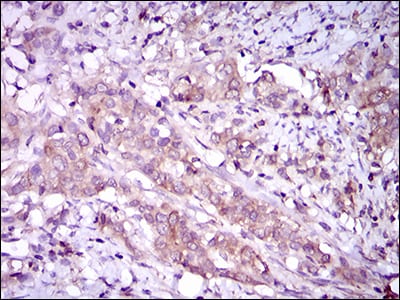

Immunohistochemical analysis of paraffin-embedded human cervical cancer tissues using MAPK14 mouse mAb with DAB staining.